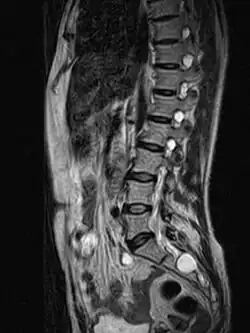

MRI image showing a Tarlov cyst | |

MRI, or Magnetic Resonance Imaging, is considered the imaging study of choice in identifying Tarlov cysts. MRI provides better resolution of tissue density, absence of bone interference, multiplanar capabilities, and is noninvasive. Plain films may show bony erosion of the spinal canal or of the sacral foramina. On MRI pictures, the signal is the same as the CSF one.